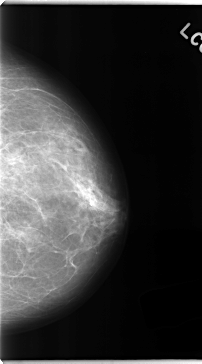

C_0149_1.LEFT_MLO

C_0149_1.LEFT_CC

LEFT_MLO LINES 4752 PIXELS_PER_LINE 2464 BITS_PER_PIXEL 12 RESOLUTION 50 NON_OVERLAY

LEFT_CC LINES 4720 PIXELS_PER_LINE 2624 BITS_PER_PIXEL 12 RESOLUTION 50 NON_OVERLAY